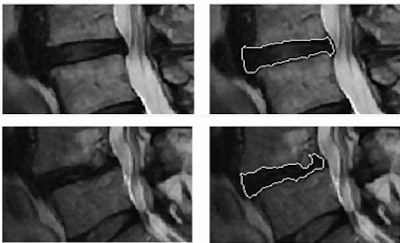

| Lumbar disk segmentation in the study was based on a hybrid algorithm combining fuzzy clustering techniques with a probabilistic disk atlas. Shape and textural features were extracted from each segmented disk region to quantify its properties. |

The disks depicted on MRI were extracted from the rest of the dataset using an Atlas process. Then shape and textural features were extracted from each segmented disk region including region descriptors, Hu's moments, Fourier descriptors, first-order textural features, and co-occurrence features.